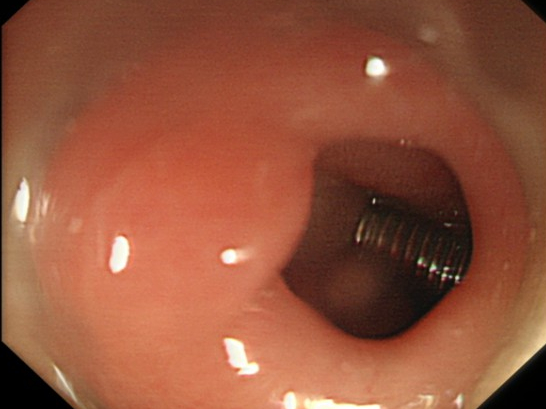

当胃镜进入患儿体内后,发现其胃内已经有多处擦伤以及陈旧性出血点,并且螺丝钉已经游走到十二指肠,再晚一步,若螺丝钉继续游走,掉入十二指肠下段等其他小肠部位,后果不堪设想。

异物取出现场

螺丝钉已经到达十二指肠球部

医护人员凭借多年的经验和密切配合,先将螺丝钉从十二指肠取出到胃内,然后不断调整螺丝钉的角度,最终顺利将螺丝钉从胃内取出。

电子胃镜直视下螺丝钉在胃内的情形